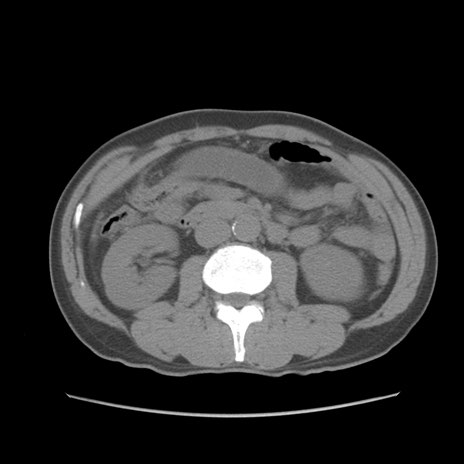

症例56 CT(横断像)

脂肪ウインドウ